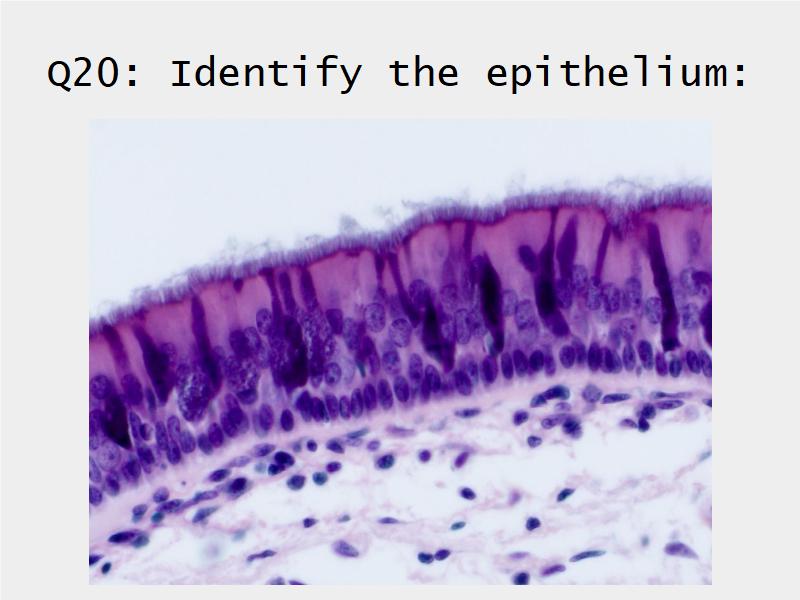

Respiratory epithelium

- Pseudostratified

- Ciliated

- Columnar

- Epithelium with

- 4 Cells

- Ciliated columnar cells

- Non-ciliated columnar cells

- Goblet cells

- Basal cells